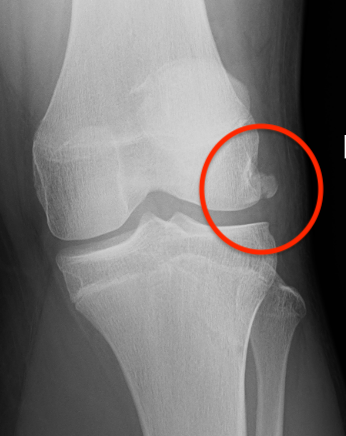

Xray

Look for osteochondral fractures

- AP xray: gutters

Loose body in lateral gutter